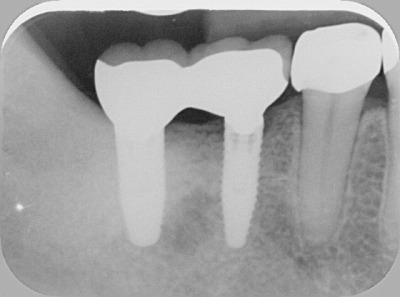

2012.04.28 院長ブログ インプラント3 今日のインプラントは、右下の奥歯に2本でした。本来なら入れ歯になる所ですが、入れなくて済んで良かったと感動されて帰りました。ゴールデンウィークに間に合ってよかったですね。 レントゲンで見るとインプラントから歯に移行する立ち上がりのラインもきれいに仕上がっています。 上の歯が少し伸びてきていて、歯の高さが十分に確保できず上からのネジ固定ですが、ネジ穴もきれいに隠れました。 陶器の色の仕上がりもキレイです。 次の記事 »インプラント2 « 前の記事インプラント矯正